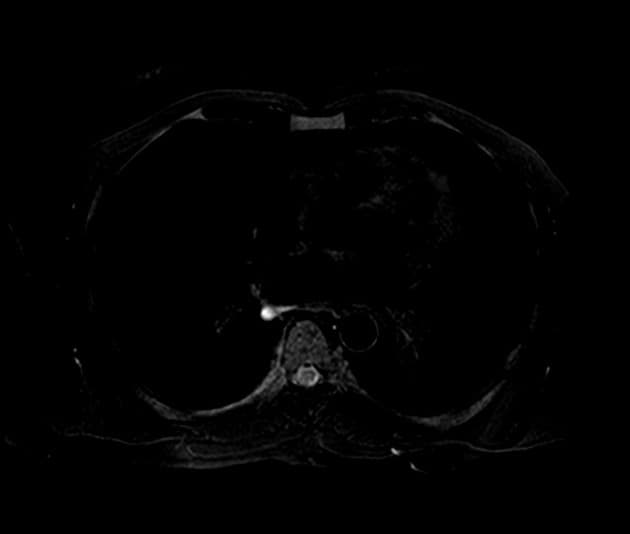

- Khối rất giới hạn rõ (well-circumscribed) ở cổ tử cung đoạn thấp, với lớp niêm mạc tử cung còn nguyên vẹn.

- U lympho cổ tử cung (lymphoma of cervix) đơn độc khá hiếm gặp và có thể biểu hiện hình ảnh với những dấu hiệu hiếm như trường hợp này.

- "Việc bảo tồn lớp niêm mạc tử cung trên hình ảnh học có thể giúp phân biệt u lympho với các khối ác tính cổ tử cung khác."

U lympho cổ tử cung là một biểu hiện ngoại hạch hiếm gặp của u lympho không Hodgkin, trong đó tổn thương khu trú riêng lẻ tại cổ tử cung là rất bất thường. Bệnh thường khởi phát với các triệu chứng không đặc hiệu như rối loạn cảm giác vùng chậu hoặc chảy máu bất thường. Chẩn đoán hình ảnh thường phát hiện khối u giới hạn rõ, có thể bắt chước các khối u lành tính như u cơ trơn hoặc các khối u ác tính biểu mô. Việc bảo tồn lớp niêm mạc tử cung, như trong trường hợp này, có thể là dấu hiệu gợi ý về nguồn gốc không phải biểu mô. Chẩn đoán chủ yếu dựa vào phân tích mô bệnh học và miễn dịch hóa học vì hình ảnh học không đặc hiệu. CT giai đoạn không thấy tổn thương hệ thống hỗ trợ chẩn đoán u lympho cổ tử cung nguyên phát đơn độc. Nhận biết rõ về bệnh lý này là rất quan trọng để tránh chẩn đoán nhầm và đảm bảo điều trị ung thư phù hợp.